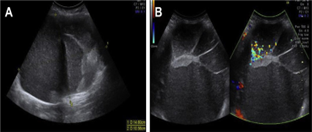

Background: The extensive use of cross-sectional abdominal imaging (CT and MRI) has led to an increase in the occurrence of pancreatic cysts (PCs). Objectives: Identifying different forms of PC lesions, discriminating between malignant and benign cysts, and determining the prevalence of neoplastic and non-neoplastic PC. Methods: A retrospective cross-sectional analysis of 120 individuals with pancreatic cystic lesions was conducted between February 2023 and February 2024. There are 45 men and 75 women. The lesions were detected by EUS, MRI, CT, and TAUS. All patients underwent an EUS-guided FNA. Cytology and tumor markers (CA19-9 and CA-125) were used to evaluate the aspirated specimens. Results: PCs were substantially more common in females (62.5%). Benign SCN was the most common kind (40%). Malignant cysts were detected in 35 patients (29.2%) (IPMN 62.9%), with men accounting for a statistically significant majority (71.4%). Malignant cysts significantly correlated with vomiting and weight loss (34.3% and 91.4%, respectively). CA-19-9 and CA-125 showed considerably larger elevations in malignant cysts than benign cysts (68.6% and 56.5%, respectively). EUS was the most effective imaging tool for cyst detection, with a sensitivity of 94.3% and a specificity of 91.8%, followed by MRI, CT scan, and TAUS. Conclusions: Females were more likely to have PCs, whereas males had more malignant cysts. The most common and benign kind of PC was SCN. The most common form of malignant PC was IPMN, and EUS was the most effective way to diagnose PCs.